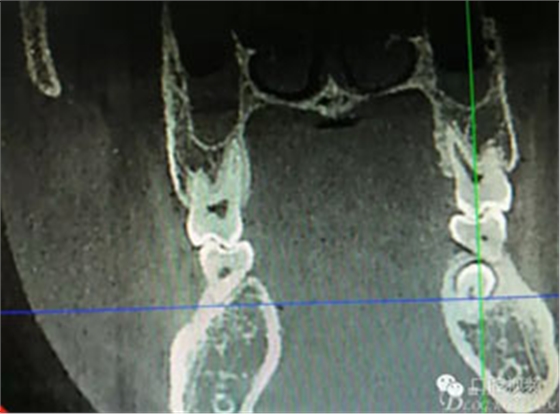

圖1.術(shù)前的全景片影像檢查,35移位至36、37之間。

圖2.術(shù)前的CBCT,35移位至36、37之間的舌側(cè)。